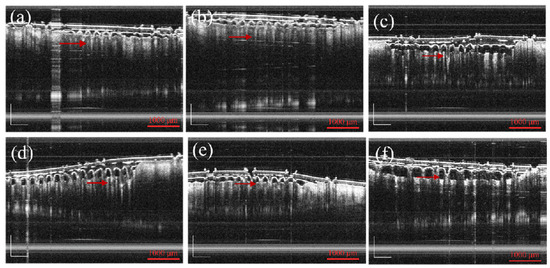

By observing the optical coherence tomography (OCT) images, it could be seen that the MNs evenly penetrated on the skin, and the penetration rate of MNs was 100%. This was consistent with the above skin penetration results. According to the OCT diagram in Figure 6, it was observed that with the increase in the Pro ratio, the skin depth of penetration entering the skin also decreased. Pro has a hygroscopic property, and the hardness of MN decreases due to this hygroscopic property. The effect of instantaneous puncture was not as good as that of the unmodified and methanol treated groups. When the Pro/MT/SF ratio was 50/1/100, there was a large gap between the chip and the skin during penetration. When the ratio was 10/1/100, 20/1/100, and 30/1/100, MNs had good adhesion. The MNs prepared in this experiment could penetrate the skin without producing a pricking sensation.

Figure 6. Optical coherence tomography images of MNs: (af) METH-treated Pro/MT/SF = 0/1/100, 10/1/100, 20/1/100, 30/1/100, and 50/1/100 (The red arrows indicate the MNs, scale bar is 1000 μm).